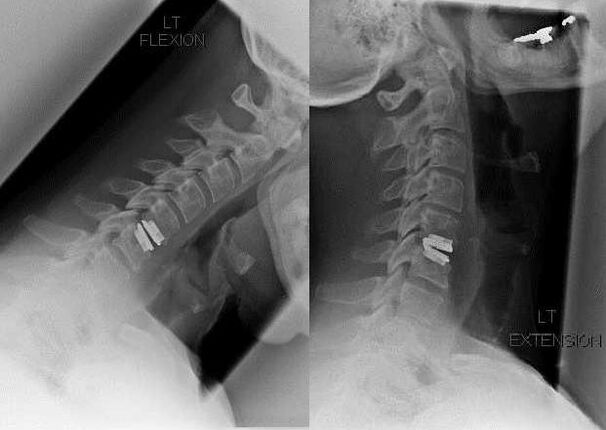

Surgical intervention

Indications for surgical intervention include the ineffectiveness of conservative treatment, as well as complications of cervical osteochondrosis, for example, discogenic myelopathy, vertebral artery syndrome and radicular syndrome.To decompress the spinal cord, blood vessels and spinal roots, the following operations are performed:

- laminectomy;

- laminotomy;

- foraminotomy;

- facetectomy;

- discectomy.

During surgery, bone fragments and ligaments can be excised and intervertebral discs can be removed in whole or in part.For small hernial protrusions, laser vaporization of the disc nucleus is often performed.

After excision of the vertebral structures, stabilization of the spinal motion segments is often required by spinal fusion or the installation of bone and dermal autografts.